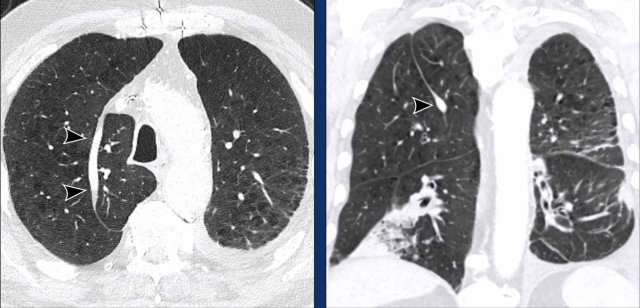

Image

There is an acute-on-chronic

occlusive segmental thrombus in the anterior segment of the left upper lobe

(black arrow).

Pre-existent segmental occlusion in of the basal

branches with acute tapering of the peripheral vessels (blue arrow).

These images are of a 53 y.o. male with pulmonary hypertension.